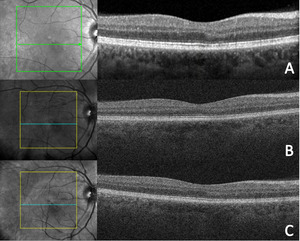

Fundus photography (California Optomap, Optos plc, Dunfermline) captured an image of the faint lesion in the right eye, whereas fundus autofluorescence imaging showed an area of subtle hyperautofluorescence (Figure 1). Optical coherence tomography (Spectralis, Heidelberg Engineering) imaging of the macula with near-infrared reflectance revealed a well-defined, hyporeflective ovoid lesion pointing toward the fovea in the right eye (Figure 2). B-scan images through the lesion demonstrated subtle outer plexiform layer hyperreflectivity and thickening, outer nuclear layer thinning, and attenuation of the ellipsoid and interdigitation zones (Figure 2).

Optical coherence tomography (Cirrus, Zeiss) imaging of the macula with near-infrared reflectance was performed using a separate imaging platform because of equipment availability. En face images identified the macular lesion within the inner segment/outer segment–ellipsoid zone slab, whereas B-scan images through the macular lesion showed stable structural findings compared with the initial visit (Figure 3).

Optical coherence tomography (Cirrus, Zeiss) of the macula demonstrated stable structural findings compared with those from the patient’s previous 2 visits (Figure 6).

Multimodal imaging of the retina with combined near-infrared reflectance and spectral domain optical coherence tomography is most sensitive in detecting acute macular neuroretinopathy. Near-infrared reflectance uses infrared light between 804 and 895 nm to image the outer retina, retinal pigment epithelium, and choroid.32 These wavelengths are closer to the visible light spectrum compared with infrared light, penetrate deep into the ocular tissues, bypass media opacities, and exhibit high reflectance from the fundus for enhanced disease detection.32 This imaging modality reveals hyporeflective, well-demarcated lesions that are more discernible than fundoscopy and have been documented up to 6 years after initial diagnosis.2,19 This patient exhibited a distinct, hyporeflective retinal lesion with near-infrared reflectance at 4, 5, and 9 months from initial symptom onset. Spectral domain optical coherence tomography has demonstrated outer plexiform and nuclear layer hyperreflectivity as early as 1 day after symptom onset.9 Most cases using spectral domain optical coherence tomography imaging detected outer retinal changes, which may include ellipsoid zone disruption, outer nuclear hyperreflectivity, and outer plexiform hyperreflectivity.2,7–9 Persistent retinal changes often consist of outer nuclear thinning and interdigitation zone disruption, which have been documented up to 16 months after initial symptom onset.7–9 Outer plexiform thickening has also been reported up to 173 days from the initial visit, whereas hyperreflective change may improve.7,8 Similarly, this patient displayed subtle outer plexiform layer hyperreflectivity and thickening, outer nuclear layer thinning, and attenuation of the ellipsoid and interdigitation zones through 9 months from initial symptom onset. Notably, the outer plexiform layer hyperreflectivity that persisted through 9 months has not previously been reported at this duration.